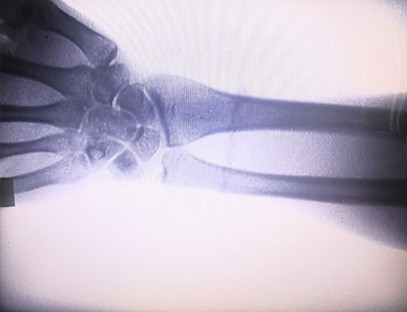

As-c200 bærbar røntgenmaskine er et bærbart instrument med lille strålingsdosis og meget sikkert. Den er især velegnet til enheder og enkeltpersoner med utilstrækkeligt budget og lave krav til billeder. Den nye generation er udstyret med en 10 tommer stor skærm i høj opløsning, som har et større perspektivområde og fuldt ud kan perspektivere hele håndfladen. Det er mest velegnet til medicinsk ortopædisk perspektiv. Den kan tilsluttes en filmprinter for at printe ortopædiske film og kan også bruges i industriel produktion og test. Intet mørkekammer, direkte perspektiv, øjeblikkelig observation, høj opløsning og klar billeddannelse.

Vores ortopædiske røntgenmaskine er et højkvalitetsprodukt, der er designet specielt til ortopædisk billeddannelse. Det kan bruges til diagnosticering og behandlingsplanlægning af forskellige ortopædiske tilstande, herunder frakturer, dislokationer, gigt og knogletumorer. Den er udstyret med avanceret røntgenteknologi, der muliggør billeder i høj kvalitet med reduceret strålingseksponering. Maskinen har et billeddannelsessystem i høj opløsning og kan tage billeder af enhver knoglestruktur med stor klarhed.

Vores ortopædiske røntgenmaskine kan bruges i forskellige medicinske specialer, herunder ortopædi, neurologi og akutmedicin. Det bruges ofte til fluoroskopisk observation af menneskelige lemmerknogler, veterinær- og kæledyrshospitaler, behandling af sårede på sportspladser, bygninger, oceangående skibe, fjerntliggende områder og militære feltsteder. Nogle af de kliniske anvendelser inkluderer: